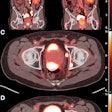

PET maximum intensity projections (MIP) of example cases in a test set with high (left), intermediate (middle), and low (right) agreement between manual expert annotation and the automated convolutional neural network (CNN)-based annotation of sites suspicious for cancer (overlayed in yellow wherever visible in the PET MIP). The number of annotated findings and miTNM nodal and metastatic stage are reported. Image courtesy of Nicolo Capobianco, PhD.The dataset included 173 prostate cancer images of patients who underwent PET/CT using F-18 DCFPyL radiotracer (Pylarify) and 193 patients who underwent PET/CT using gallium-68 (Ga-68) PSMA radiotracer. Both PET tracers are approved in the U.S. In training, the group ultimately pooled data for both tracers, Capobianco noted.

The AI model matched the expert's assessment of local and nodal cancer in 65% of cases that used F-18 DCFPyL and 79% of cases for Ga-68 PSMA-11; for metastatic lesions, the AI model matched the expert's assessment in 73% of cases that used F-18 DCFPyL and 75% cases that used Ga-68 PSMA-11, according to the findings.